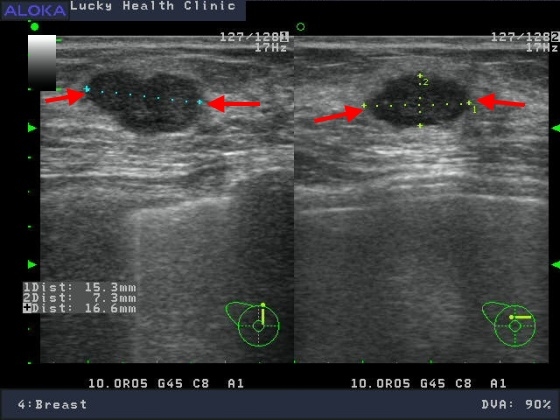

醫學影像..乳房超音波

分類 4:懷疑不正常,惡性度 2%~95%(建議切片)